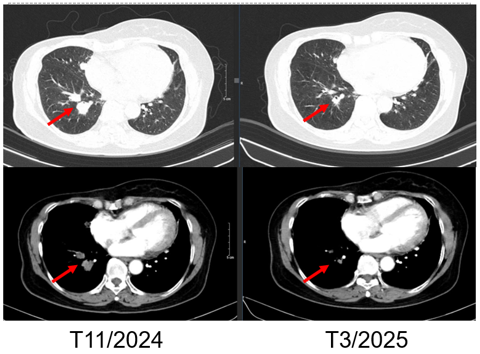

SO SÁNH TRƯỚC VÀ SAU ĐIỀU TRỊ

Hình 4. Hình ảnh chụp CT ngực trước và sau điều trị: Tổn thương tái phát thành ngực

Hình 5. Hình ảnh chụp CT ngực trước và sau điều trị: Tổn thương phổi trái

Hình 6. Hình ảnh chụp CT ngực trước và sau điều trị: Tổn thương phổi phải

- Chụp cắt lớp vi tính ngực:

+ Thành ngực phải có nốt đặc đường kính 5mm – theo dõi tổn thương tái phát

Phổi phải: nhu mô thuỳ giữa và dưới có các khối – nốt đặc, lớn nhất 7x8mm

+ Phổi trái: nhu mô thuỳ trên và đáy phổi sát màng phổi có các khối nốt đặc, lớn nhất 9x8mm